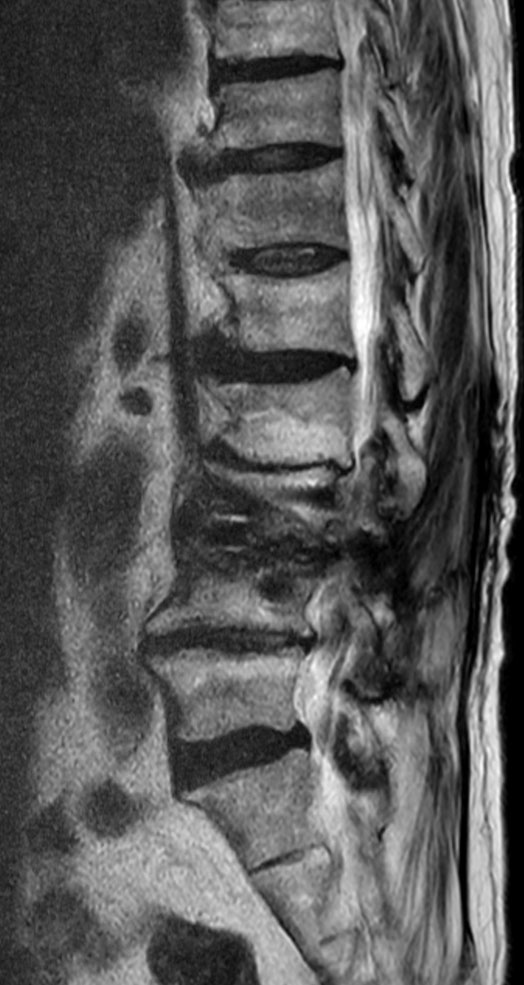

Sagittal T1w TSE O-MAR (VAT) 1